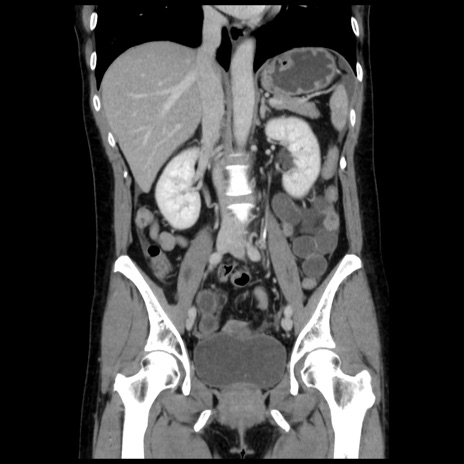

症例10(冠状断像)

【症例】 50歳代女性

【主訴】 腹痛

【現病歴】前日生レバーを食べた。今朝に排便あり。 昼前に突然発症の腹痛を生じ、当院救急外来を受診した。

【既往歴】 子宮筋腫にてで子宮全摘後

【身体所見】 意識清明、腹部:平坦、軟、下腹部やや左を中心に圧痛・反跳痛あり、筋性防御あり

【データ】WBC 7800、CRP 0.07